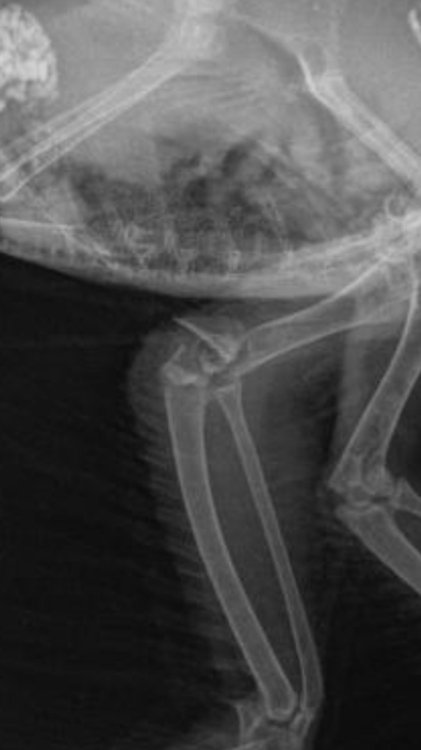

Добрый вечер. Подобрали птенца чайки со сломанной лапкой. Открытый перелом правой лапки. Чайку прооперировали. Поставили спицы. Лапка восстанавливается. Левая лапка была здоровая. Но при транспортировки к орнитологу, что-то случилось с лапкой. Держит в согнутом виде, не выпрямляет и не встает. Делали рентген. На нем нет вывихов и переломов левой лапки. Снимок рентгена перед операцией. повредили левую лапку 29.06.2024 операция правой лапки была 02.07.2024. Данный снимок был сделан 06.07.2024 16.07.2024 делали повторный рентген, чтобы проверить правую лапку после операции. Левую тоже смотрел неоднократно, но никто из врачей не может сказать что с левой лапкой. Подскажите пожалуйста, что может быть с левой лапкой, как восстановить? Для птенца сделаны качели, чтобы снизить нагрузку на лапы.